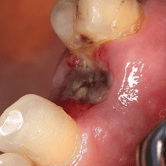

Extracción de Muelas del Juicio

La extracción de las muelas del juicio es un procedimiento quirúrgico para remover los terceros molares que pueden causar dolor, infección o daño a otros dientes debido a su posición o crecimiento anómalo.

Los pacientes pueden experimentar dolor, hinchazón y, en algunos casos, infección alrededor de estas muelas.

El tratamiento incluye la extracción quirúrgica para prevenir o resolver complicaciones.